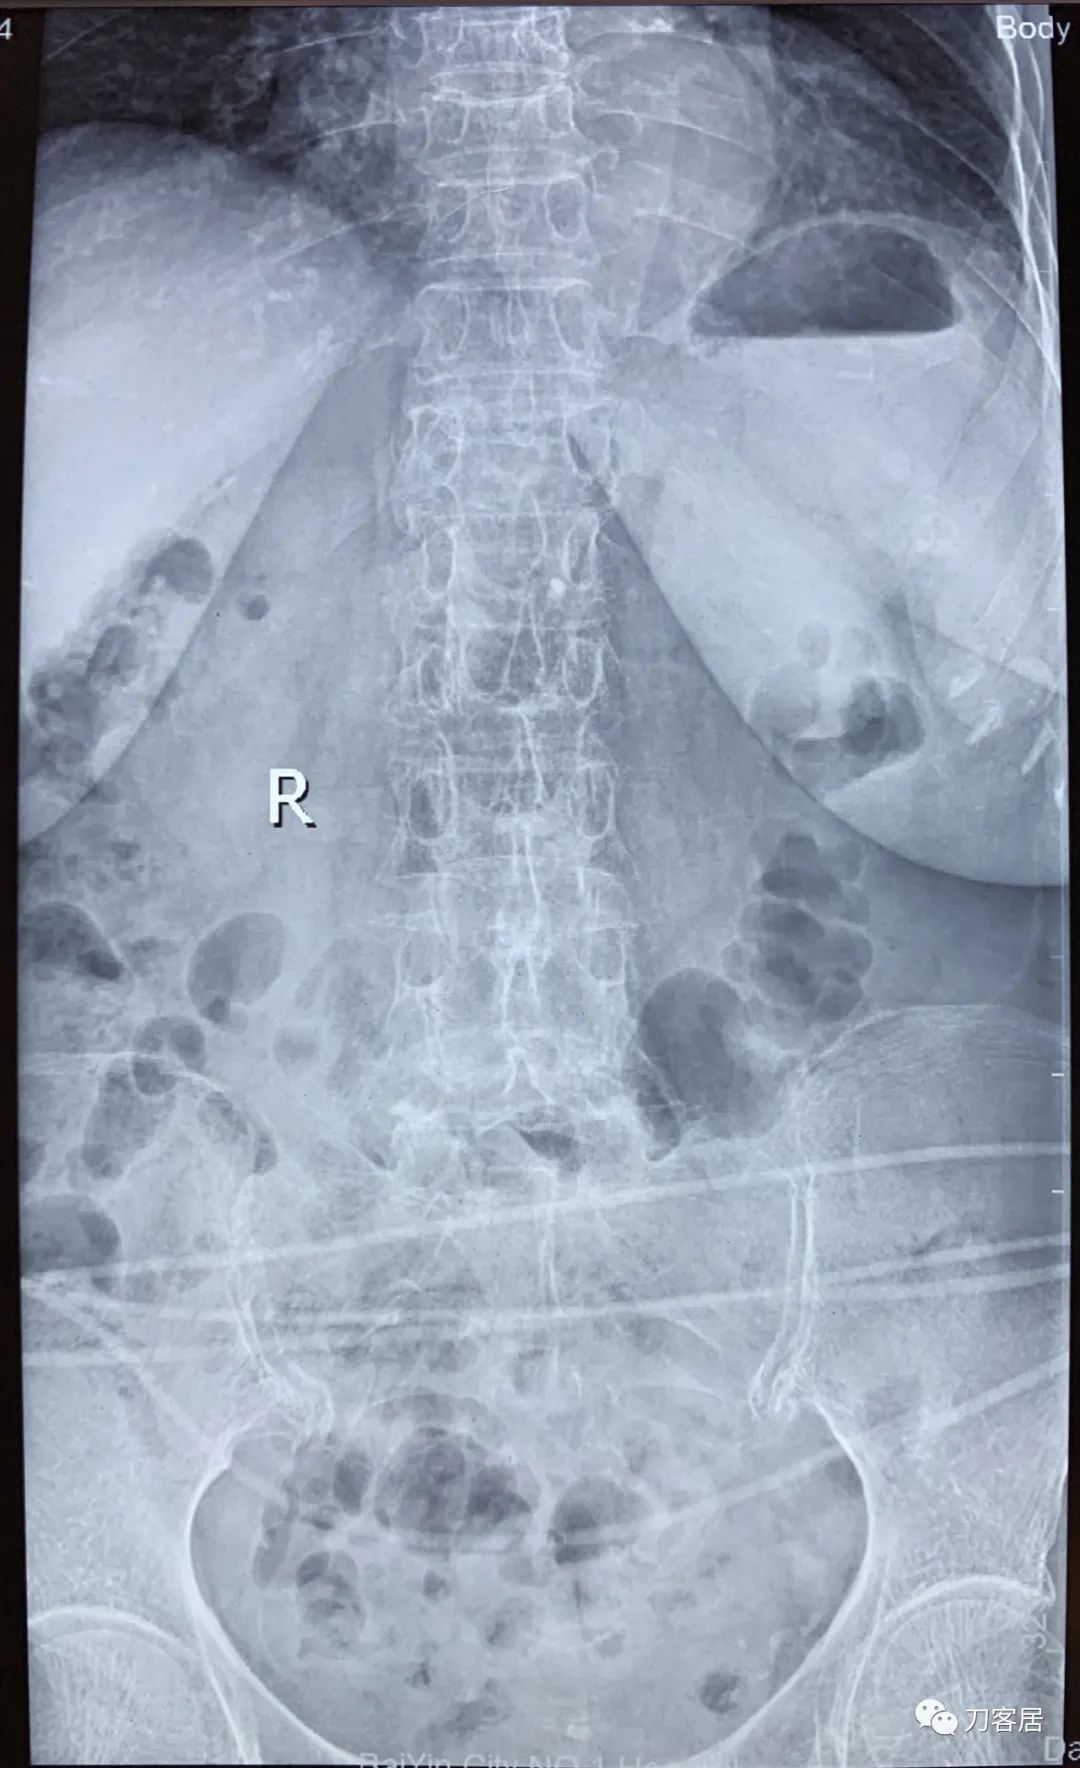

自带影像学资料提示胸椎,腰椎多发脊柱压缩性骨折。

诊断 : 重度骨质疏松症,胸椎、腰椎多发椎体压缩性骨折

图03-20200825腰椎正位X线片

图04-20200825腰椎侧位X线片